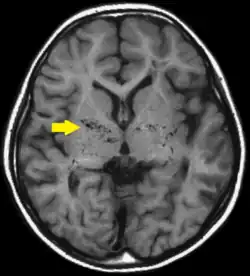

Choroba moyamoya, choroba moya-moya (jap. もやもや病, dosł. mglisty, mętny, rozmyty) – rzadki zespół chorobowy o nieznanej etiologii, występujący głównie u młodych (dzieci i młodzi dorośli) Azjatów, powodujący niedrożność dużych tętnic wewnątrzczaszkowych, szczególnie końcowego odcinka tętnicy szyjnej wewnętrznej i tętnic środkowej i przedniej mózgu, doprowadzając do niedokrwienia ośrodkowego układu nerwowego, przebiegającego najczęściej pod postacią przemijających napadów niedokrwiennych, choć może również przebiegać jako udar mózgu lub krwotok mózgowy.

Podstawą rozpoznania jest obraz angiograficzny mózgu, gdyż widoczne są na nim licznie rozwijające się naczynia krążenia obocznego, tworzące charakterystyczne dla tej choroby „kłęby dymu”.